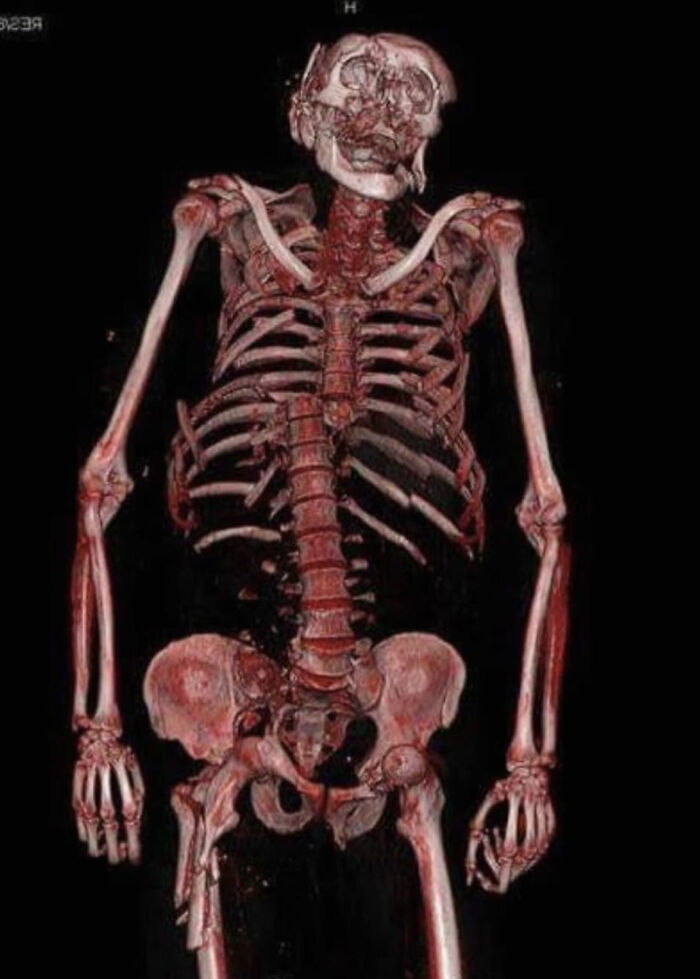

This 3D CT Scan Shows Multiple Fractures As The Result Of A Motorcycle Accident At High Speed

Ouch. I came close, hitting the armco barrier backwards and upside down at high speed. Thankfully, at least in part due to the back protection built in to my jacket, the vertebrae shattered but did not move, all the ribs were broken, but at the front, showing how the impact had been transferred away from the spine by said protection. I haven't ridden a motorcycle since, now nearly 20 years ago, scan0002-6...89e800.jpg